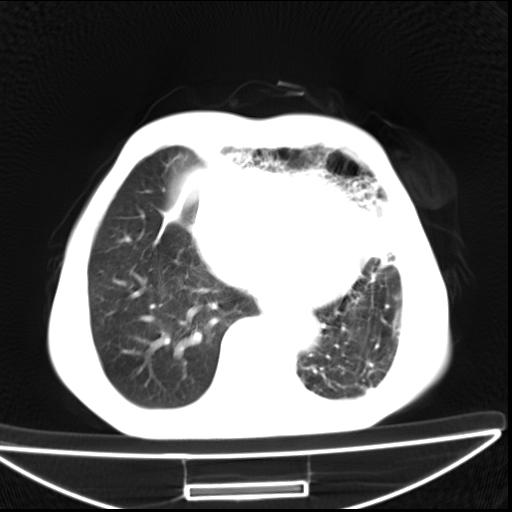

男  70岁,发烧咳嗽4天。盗汗,消瘦。无痰中带血丝,以前有肺tb病史,ct见,双肺tb,左侧胸廓塌陷,左胸膜肥厚粘连。纵隔移位,右侧胸腔积液,大家说说那个心影前左肺舌叶除了肺大炮还有炎症还是干酪性肺炎?有占位吗?我看纵隔淋巴结也大。

1)两肺继发性肺结核并左肺上叶肺不张,支气管扩张。2)双侧胸膜炎(胸膜增厚+少量胸腔积液)。

两肺继发性肺结核并感染,左肺上叶肺不张。建议ct增强。